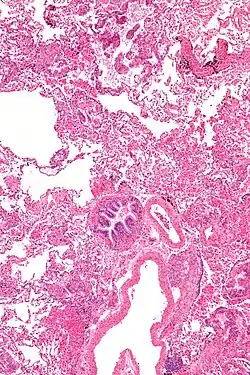

Pathology

Grossly, LAM lungs are enlarged and diffusely cystic, with dilated air spaces as large as several centimeters in diameter.[105][106] Microscopic examination of the lung reveals foci of smooth muscle-like cell infiltration of the lung parenchyma, airways, lymphatics, and blood vessels associated with areas of thin-walled cystic change. LAM lesions often contain an abundance of lymphatic channels, forming an anastomosing meshwork of slit-like spaces lined by endothelial cells. LAM cells generally expand interstitial spaces without violating tissue planes but have been observed to invade the airways, the pulmonary artery, the diaphragm, aorta, and retroperitoneal fat, to destroy bronchial cartilage and arteriolar walls, and to occlude the lumen of pulmonary arterioles.[105]

There are two major cell morphologies in the LAM lesion: small spindle-shaped cells and cuboidal epithelioid cells.[107] LAM cells stain positively for smooth muscle actin, vimentin, desmin, and, often, estrogen and progesterone receptors. The cuboidal cells within LAM lesions also react with a monoclonal antibody called HMB-45, developed against the premelanosomal protein gp100, an enzyme in the melanogenesis pathway.[107] This immunohistochemical marker is very useful diagnostically, because other smooth muscle-predominant lesions in the lung do not react with the antibody.[108] The spindle-shaped cells of the LAM lesion are more frequently proliferating cell nuclear antigen positive than the cuboidal cells, consistent with a proliferative phenotype.[107] Compared with cigar-shaped normal smooth muscle cells, spindle-shaped LAM cells contain less abundant cytoplasm and are less eosinophilic. Estrogen and progesterone receptors are also present in LAM lesions,[109][110][111] but not in adjacent normal lung tissue.[112] LAM lesions express lymphatic markers LYVE-1, PROX1, podoplanin and VEGFR-3. The smooth muscle-like cells of AMLs are morphologically and immunohistochemically similar to LAM cells, including reactivity with antibodies directed against actin, desmin, vimentin, and HMB-45 as well as estrogen and progesterone receptors.[113][114] Unlike the dilated airspaces in emphysema, the cystic spaces found in LAM may be partially lined with hyperplastic type II cells.[115]